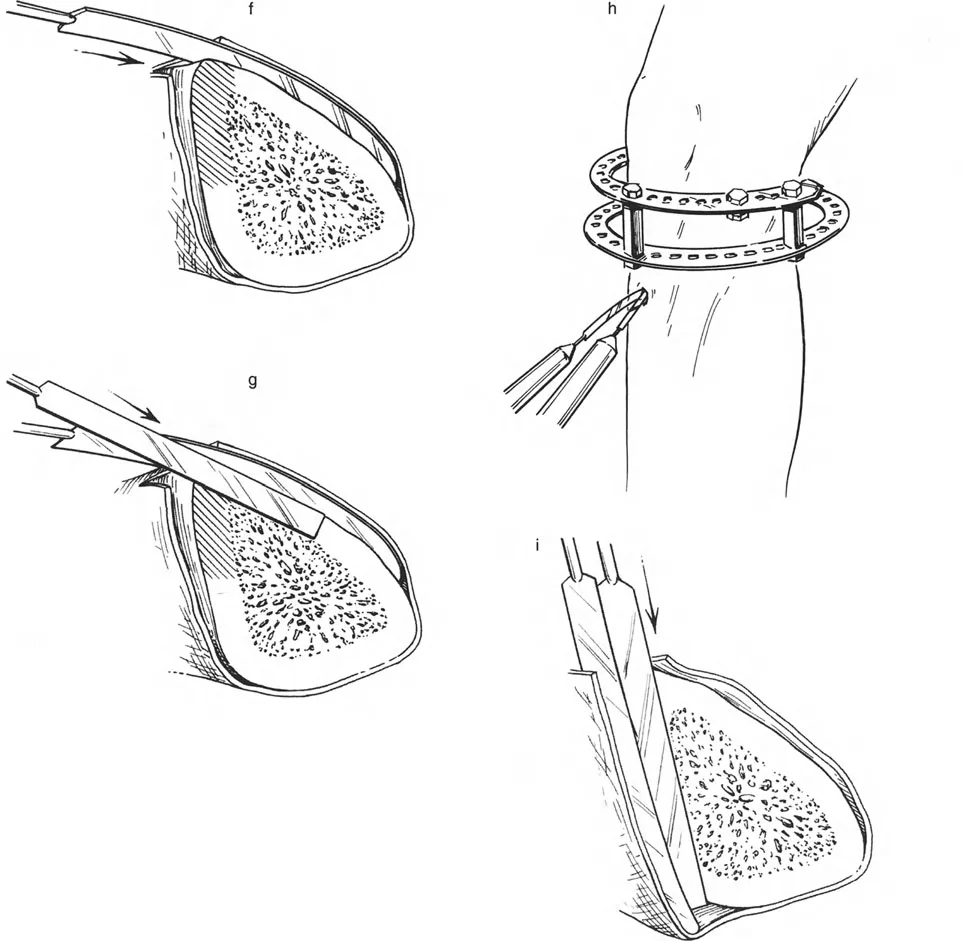

قبل الخوض في تفاصيل الأجهزة الميكانيكية، من الضروري فهم الركيزة البيولوجية التي نتعامل معها. اكتشف إليزاروف أن الأنسجة الحية، عندما تتعرض لشد بطيء وثابت، تصبح نشطة أيضيًا. هذا "تأثير الشد والضغط" يحفز تكوين العظم (osteogenesis)، وتكوين الأوعية الدموية (angiogenesis)، وتكوين الأنسجة الأخرى (histogenesis) مثل العضلات والأعصاب والجلد.

ومع ذلك، تعتمد هذه "المعجزة البيولوجية" بشكل كبير على الاستقرار الميكانيكي. إذا كان المثبت الخارجي شديد الصلابة، فقد لا يتكون العظم الجديد بشكل كافٍ؛ وإذا كان فضفاضًا جدًا، فإن قوى القص ستدمر الأوعية الدموية الدقيقة التي تتشكل في الفجوة، مما يؤدي إلى تكوين غضروف ليفي وعدم التحام العظم. يجب أن يوفر الجهاز حركة محورية دقيقة مع منع قوى القص وعدم الاستقرار الدوراني بشكل صارم.

المفصلات القريبة من المفصل وقواعد قطع العظم (Osteotomy Rules)

عند التعامل مع التشوهات الواقعة بالقرب من خط المفصل - مثل التقوس الشديد في الجزء العلوي من الساق (مرض بلونت) أو التشوه الفحجي في الجزء السفلي من عظم الفخذ - يصبح وضع الجهاز مقيدًا هندسيًا. إن المتطلبات البيولوجية للحفاظ على كبسولة المفصل، وتجنب وضع الأسلاك داخل المفصل، ومنع التهاب المفاصل القيحي، غالبًا ما تجبر الجراح على وضع الحلقة المرجعية على مستوى مختلف تمامًا عن مركز دوران الانحراف (CORA) الفعلي.

إذا كان مركز دوران الانحراف (CORA) يقع بالقرب من خط المفصل، فإن وضع حلقة إليزاروف القياسية عند هذا المستوى بالضبط مستحيل دون انتهاك مساحة المفصل أو شد الهياكل الكبسولية الحيوية. لذلك، يتم تثبيت الحلقة المرجعية بالعظم الكثيف أو العظم الطويل المتاح، ويتم بناء آلية المفصلة باستخدام قضبان ملولبة، ولوحات توصيل، ودعامات. ثم يتم "إنزالها" (أو رفعها) لتتطابق تمامًا مع مركز دوران الانحراف (CORA) الهندسي الحقيقي.